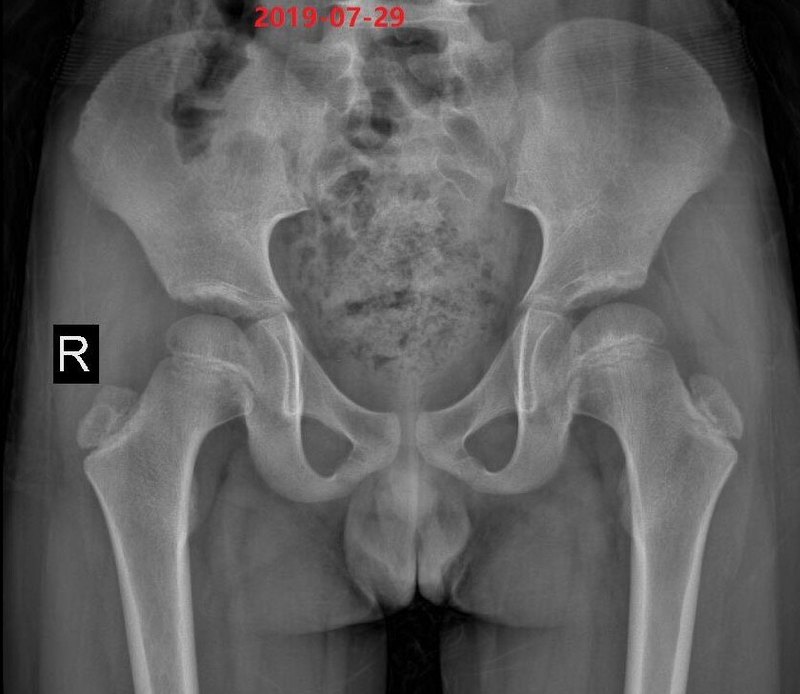

Perthes病一個(gè)典型特點(diǎn)是屬于“自限性疾病”,一般會(huì)經(jīng)歷缺血壞死、碎裂、修復(fù)、愈合等幾個(gè)階段,這就是Perthes病的病程,或者說(shuō)臨床分期。1910年,除了美國(guó)的Arthur Thornton Legg、法國(guó)的Jacques Calvé和德國(guó)的Georg Perthes等三位醫(yī)生外,最早描述Perthes病疾病演變、不同階段有不同影像學(xué)表現(xiàn)的是瑞典的Henning Waldenstrm醫(yī)生(1909年,patho-histologic evaluation and radiographic staging)。有意思的是,當(dāng)時(shí)這幾名醫(yī)生對(duì)該病的發(fā)病原因解釋各不相同。Legg認(rèn)為與創(chuàng)傷有關(guān),Perthes認(rèn)為是“葡萄球菌的感染”,Calvé考慮屬于骨發(fā)育異?;蜓舆t,Waldenstrm醫(yī)生則認(rèn)為源于結(jié)核感染。一百多年過(guò)去了,雖然大家把該病命名為L(zhǎng)egg-Calvé-Perthes Disease,但是,Waldenstrm最早提出的疾病分期時(shí)至今日仍被廣泛應(yīng)用于臨床,同樣對(duì)Perthes病的認(rèn)識(shí)有著巨大的貢獻(xiàn)?;赬線片表現(xiàn),Waldenstrm將Perthes病分為四個(gè)期:缺血期(Osteonecrosis stage)、碎裂期(Fragmentation stage)、修復(fù)期(Reossification stage)和愈合期(Healed stage)。Waldenstrm分期(迄今仍為唯一的分期)為什么時(shí)至今日仍被廣泛應(yīng)用于臨床?因?yàn)椴粌H僅闡明了各期影像學(xué)表現(xiàn)的差異,更重要在于,不同的影像學(xué)分期對(duì)應(yīng)著不同的“病理過(guò)程”,而這些都與臨床治療決策的選擇密切相關(guān)。缺血期(Osteonecrosis stage):病理上亦為缺血期/“Ischemic stage”。不明原因引起股骨頭血供異常,靜脈回流障礙/淤滯。Perthes病發(fā)病最初X線片表現(xiàn)不明顯,可僅有“髖關(guān)節(jié)滑膜炎”等表現(xiàn),典型的影像學(xué)改變常始于發(fā)病3-6個(gè)月后。股骨頭骺變小,密度增高(與“鈣鹽沉積”有關(guān)),關(guān)節(jié)滲出及股骨頭軟骨相對(duì)增厚致髖關(guān)節(jié)間隙“增大”。此期臨床癥狀多不顯著,持續(xù)0-8個(gè)月。碎裂期(Fragmentation stage):病理上為血運(yùn)修復(fù)/重建期-vascular repair stage。在缺血期,股骨頭骺雖缺血然而形態(tài)尚變化不顯。隨著血運(yùn)逐漸恢復(fù),破骨活躍,壞死骨被破骨細(xì)胞清理并代之以纖維組織(Catterall et al JBJS-Br, 1976)、無(wú)成骨活動(dòng)(McKibbon & Ralis JBJS-Br, 1974)。故此,碎裂期本質(zhì)上為“吸收/廓清”的過(guò)程(類似于“缺血再灌注損傷”?)強(qiáng)度變?nèi)醯墓晒穷^在過(guò)載(overloading)下逐漸塌陷變形。此期患兒行走跛行、髖關(guān)節(jié)疼痛等臨床癥狀最顯著,炎癥相關(guān)指標(biāo)(inflammatory markers)處于最高水平。結(jié)合股骨頭變形相關(guān)因素分析,在護(hù)理時(shí),需強(qiáng)調(diào)較嚴(yán)格免負(fù)重,避免對(duì)于力學(xué)脆弱的股骨頭施加過(guò)大的載荷。此期常持續(xù)6~12個(gè)月。修復(fù)期(Reossification stage):典型表現(xiàn)為新骨形成,由外向內(nèi)、由后向前。此期大約持續(xù)18~24個(gè)月。此期股骨頭骺力學(xué)強(qiáng)度逐漸恢復(fù),可無(wú)需嚴(yán)格免負(fù)重,開(kāi)始部分負(fù)重,逐漸恢復(fù)日?;顒?dòng)。愈合期(Healed stage):股骨頭進(jìn)入愈合或塑形階段,骨小梁結(jié)構(gòu)逐漸形成。印度的Benjamin Joseph醫(yī)生通過(guò)對(duì)大量Perthes病病例自然進(jìn)程(natural history)的系列觀察,發(fā)現(xiàn)股骨頭骺在碎裂早期變形及突出輕微、而在晚期則嚴(yán)重得多。如下圖顯示股骨頭突出比例隨疾病分期變化的關(guān)系。而股骨頭突出、包容不良會(huì)大大增加變形的幾率。此外,Joseph等的一項(xiàng)回顧性研究證實(shí),在壞死期或碎裂早期接受股骨近端截骨手術(shù)治療的病例,與碎裂晚期或之后病例相比,前者獲得“股骨頭圓”的幾率為后者的16倍。Salter等認(rèn)為早期良好的包容可以通過(guò)髖臼對(duì)股骨頭新生編織骨的力學(xué)塑形達(dá)到頭圓頭臼匹配,Joseph則提出待病程進(jìn)展到晚期,股骨頭往往已發(fā)生不可逆畸形變,只能進(jìn)行拯救性手術(shù)治療以盡可能的減小畸形修復(fù)后早發(fā)骨性關(guān)節(jié)炎的概率。因此,Joseph等建議將碎裂期進(jìn)一步細(xì)分成碎裂早期和碎裂晚期,以指導(dǎo)臨床治療決策。在此基礎(chǔ)上,形成了包含七個(gè)疾病分期的改良Waldenstrm分期,改良分期系統(tǒng)經(jīng)進(jìn)一步證實(shí),認(rèn)為一致性非常理想。壞死早期(1a期):股骨頭骺變小,部分或全部缺血,無(wú)高度丟失壞死晚期(1b期):頭骺缺血,有高度丟失但無(wú)碎裂碎裂早期(2a期):缺血的股骨頭骺開(kāi)始碎裂,在正位或蛙式位片上出現(xiàn)1或2個(gè)縱向裂隙碎裂晚期(2b期):股骨頭骺完全碎裂、塌陷,無(wú)新骨形成修復(fù)早期(3a期):在新獲供血頭骺周邊新骨形成,新生骨為不成熟編織骨,結(jié)構(gòu)異常。外側(cè)新生骨密度低,范圍小于頭骺寬度1/3修復(fù)晚期(3b期):新生骨密度變正常,范圍超過(guò)頭骺寬度1/3愈合期(4期):修復(fù)完全,不可見(jiàn)壞死骨及不成熟編織骨對(duì)于Perthes病,了解疾病分期的臨床意義非常大:1)有助于預(yù)測(cè)疾病自然進(jìn)程;2)基于病程選擇適宜、及時(shí)的治療時(shí)機(jī);3)指導(dǎo)臨床護(hù)理特別為是如何負(fù)重提供影像學(xué)依據(jù);4)有利于界定重要的“預(yù)后相關(guān)因素”;5)有利于不同研究中心進(jìn)行比較研究。Benjamin Joseph等基于改良Waldenstrm分期,按治療對(duì)預(yù)后的影響程度,將治療干預(yù)分為三大類,即干預(yù)性治療(preventive intervention),補(bǔ)救性治療(remedialsurgery)及挽救性治療(salvagesurgery),并以醒目的綠、黃和紅色進(jìn)行區(qū)分。